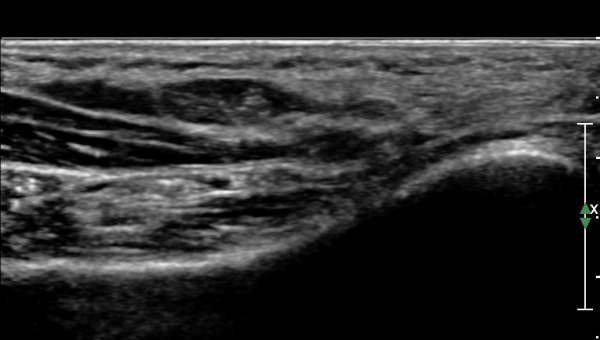

ÃÊÀ½ÆÄ°Ë»ç :  ¹ßµÚ²Þ ³»Ãø¿¡¼­ ¾Æ·¡µÚ²ÞÄ¡½Å°æ(inferior calcaneal nerve : Baxter's nerve) Ⱦ´Ü¸é °Ë»ç»ó

¹«Áö¿ÜÀü±Ù°ú Á·Àú¹æÇü±Ù(quadratus plantae) »çÀÌ¿¡¼­ ¾Æ·¡ µÚ²ÞÄ¡µ¿¸Æ ÈĹ濡 ¾Æ·¡µÚ²ÞÄ¡½Å°æÀÌ

Àú¿¡ÄÚ ¸ð¾çÀ¸·Î °üÂûµÈ´Ù(»çÁø 1, 2).